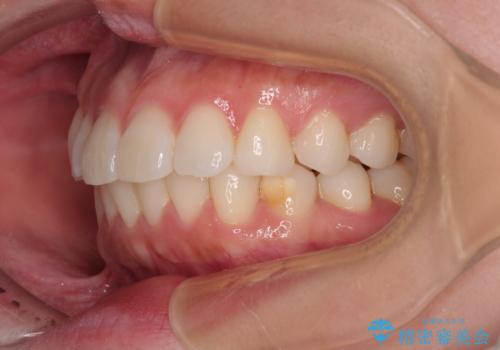

- 上下前歯の叢生を気にして来院された患者様です。

軽度な叢生であり、安価で短期間の治療を規模されていたため、インビザライン・モデレートを用いて矯正治療を行うこととしました。

インビザライン・モデレートは、製作できるアライナーの枚数に制限があるため、移動可能な量に限りがあるものの、インビザライン・ライトよりも枚数が多いため、幅広い症例に対応可能です。